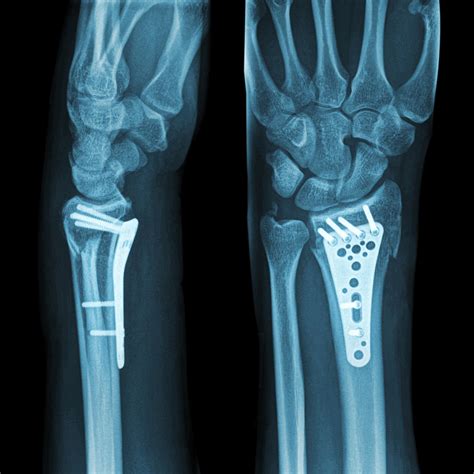

Video: Distal Radius 🪛 Plate and Screws #shorts